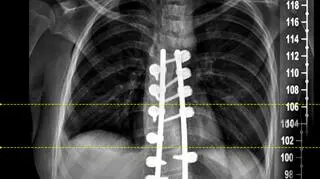

Nowatorska operacja kręgosłupa

Dzięki lekarzom ze Szpitala Zdroje w Szczecinie to się zmieniło. W poniedziałek Natalia przeszła nowatorską operację, polegającą na wstawieniu specjalnych prętów korekcyjnych, które wyprostowały jej kręgosłup.

Pręty zamówiono na miarę we Francji. Jak dowiedziała się reporterka TVN24, dobrano je na podstawie zdjęć rentgenowskich. Pod uwagę trzeba było wziąć długość odcinka kręgosłupa oraz kąt skrzywienia, a to w przypadku 13-latki wynosiło ponad 80 stopni.

- Ta operacja była wyjątkowa z uwagi na zastosowanie tego systemu przy tak zaawansowanej skoliozie, tutaj można regulować każdy jeden krąg. Korekcja kręgosłupa jest natychmiastowa, a pacjent zyskuje od razu kilka centymetrów - tłumaczy Sławomir Zacha, ortopeda, który przeprowadził operację.

Zdjęcie po operacji